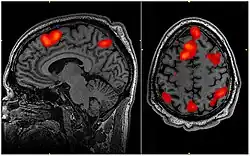

This specific FMRI scan determined which areas of the brain are activated during working memory tasks, but this type of imaging could also determine the areas of brain activated during flow experiences.

The neuroscientific underpinnings of flow are a developing field with significant potential. With advancements in neuroimaging technologies, as highlighted by Linden (2021), the opportunity to correlate psychological experiences of flow with their physiological counterparts becomes increasingly feasible.[124]